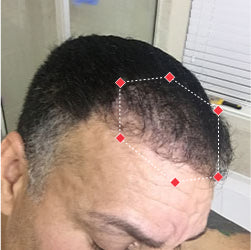

Indications for Use

The iRESTORE Hair Growth System Elite is indicated to promote hair growth in males who have Norwood-Hamilton Classifications of IIa to V and in females who have Ludwig-Savin Classifications I to II, and in both with Fitzpatrick Skin Phototypes I to IV. In other words, iRESTORE is not intended for people who are bald or have advanced hair loss.

Laser therapy works to reactivate thinning and dormant hairs. For completely bald areas of the scalp, there may be no way to promote hair regrowth. If you still have hair follicles, laser therapy may be beneficial to you.

Not sure? Email us to have our specialists evaluate your scalp conditions to see if iRESTORE is suitable for you.